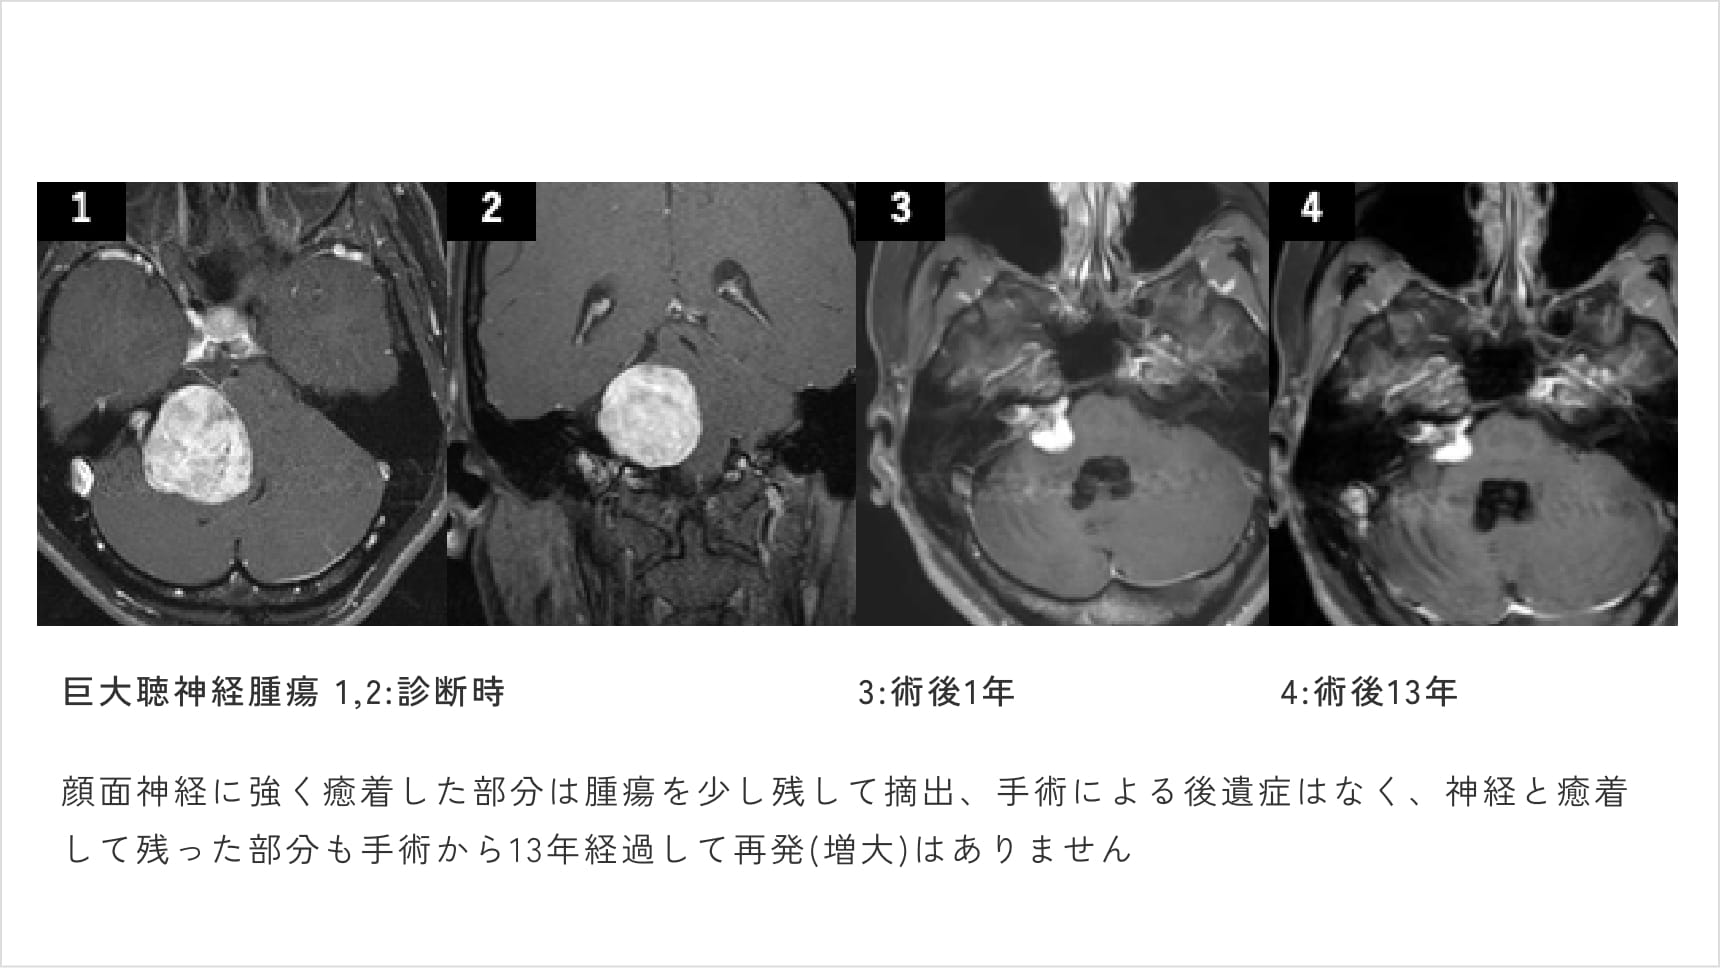

なかでも聴神経腫瘍の治療に関しては、当科が特に高い専門性を有しています。当科主任はこれまでに230例を超える聴神経腫瘍の摘出手術を執刀しており、顔面神経の温存はもちろん、可能な限り聴力の温存も目指した、精緻で丁寧な手術を行っています(図7)。

図7

また、日本聴神経腫瘍研究会認定医としての立場から、手術・放射線治療・経過観察といった選択肢の中で、患者さんにとって最も安全で適切な治療方針を提案しています。

そして何よりの強みは、これまでに400名を超える患者さんの治療や経過観察を、20年以上にわたり継続的に診療してきた実績です。治療を行った方だけでなく、経過観察を続けてきた方々の長期的な自然経過と治療効果を、実体験として熟知していることが、当科の大きな特長です。

近くの病院で直径4センチの聴神経腫瘍と診断され、非常に驚きました。

知人から「河本先生に手術してもらうと良い」と聞き、獨協医大ではなく那須赤十字病院に移られたことを知り、こちらでお世話になることにしました。

手術は約6時間かかりましたが、顔面神経に密着した部分を除き、腫瘍の98%を摘出。顔の動きや聴力にも影響はなく、まったく後遺症もありません。

術後1週間で退院し、早々にもとの生活に完全に戻ることができました。

信頼できる先生に巡り会えて本当に良かったです。